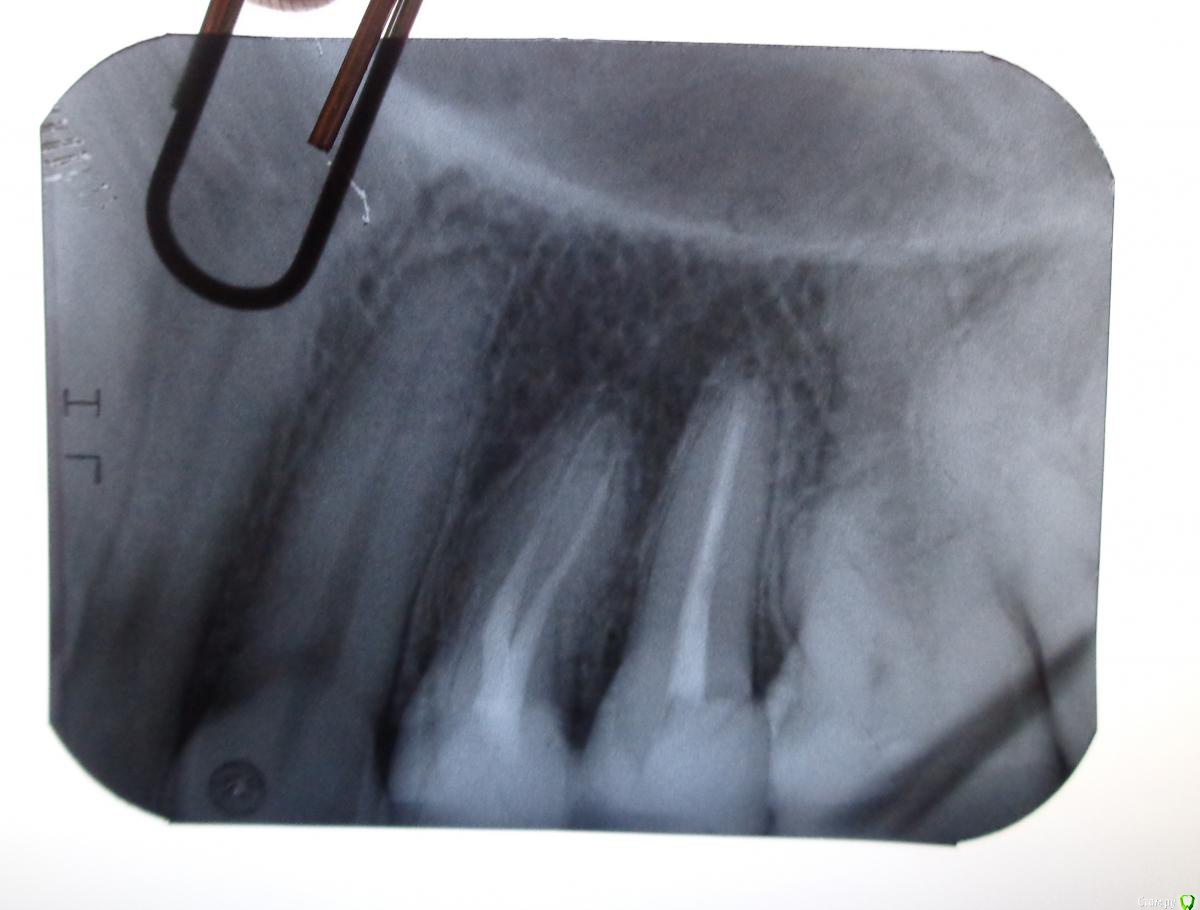

Nadyushka1231 Опубликовано 27 декабря, 2016 Поделиться Опубликовано 27 декабря, 2016 Здравствуйте! Зуб 15 меня совершенно никак не беспокоил, но на осмотре 10 октября врач сказал что есть маленький кариес, но закончилось всё удалением нерва из зуба. 10 дней ныла вся верхняя челюсть, боль отдавала в ухо и в зуб 13 (клык я так думаю болел от укола, т.к. потом мне жаловалась моя знакомая на боль в клыке после удаления нерва у того же врача), при обращении к врачу с этим вопросом (3 раза за 10 дней) на 3й раз меня просто выгнали с тем, что якобы я больна на голову, болеть в зубе нечему. Я пошла к другому врачу в стомат.поликлинику. Из за болей меня отправили на физ. процедуры (лазер+электрофорез). За неделю боль утихла. 25 октября был установлен стекловолоконный штифт и пломба световая. Ночью я поняла что зуб стал снова болеть, но я подумала что болит он от вмешательства. Терпела еще несколько дней, после чего пошла к врачу, но и этот врач мне сказал, что болеть нечему. В середине ноября меня снова отправили на лазер+электрофорез. Потом я пошла к парадонтологу, в надежде на то что боли дает десна, но пародонтолог тоже ничего не увидела, и в целях профилактики отправила меня на лезер на все десна. Зуб как болел так и продолжил болеть. Я поехала в другой город в стомат.клинику. Врач по рентгену тоже ничего не увидел и выписал пропить Ципролет. Я пропила, но боли не прошли. Вот уже прошло 2,5 месяца с момента удаления нерва. Зуб болит при надавливании, при постукивает, болит пол челюсти, боль отдает в область перед ухом. 22 декабря делала рентген этого зуба, но врач снова не видит ничего на рентгене. Сказал что зуб запломбирован нормально, воспаления и кист на корне нет, десна не воспалена. Вот я теперь совсем не знаю что мне делать.... Раньше он меня совсем не беспокоил а теперь уже больше 2 месяцев я мучаюсь с болью и никто не может мне помочь. Соседние зубы при надавливании, постукивании не болят совсем, на холод не реагируют. Боль именно в зубе 15. Посоветуйте пожалуйста, что мне делать?Фото прикрепляю до установки штифта (середина октября), 2 рентген (конец ноября). Последнего рентгена из другого города к сожалению у меня нет, но врач сказал что по последнему рентгену всё нормально. Ссылка на комментарий